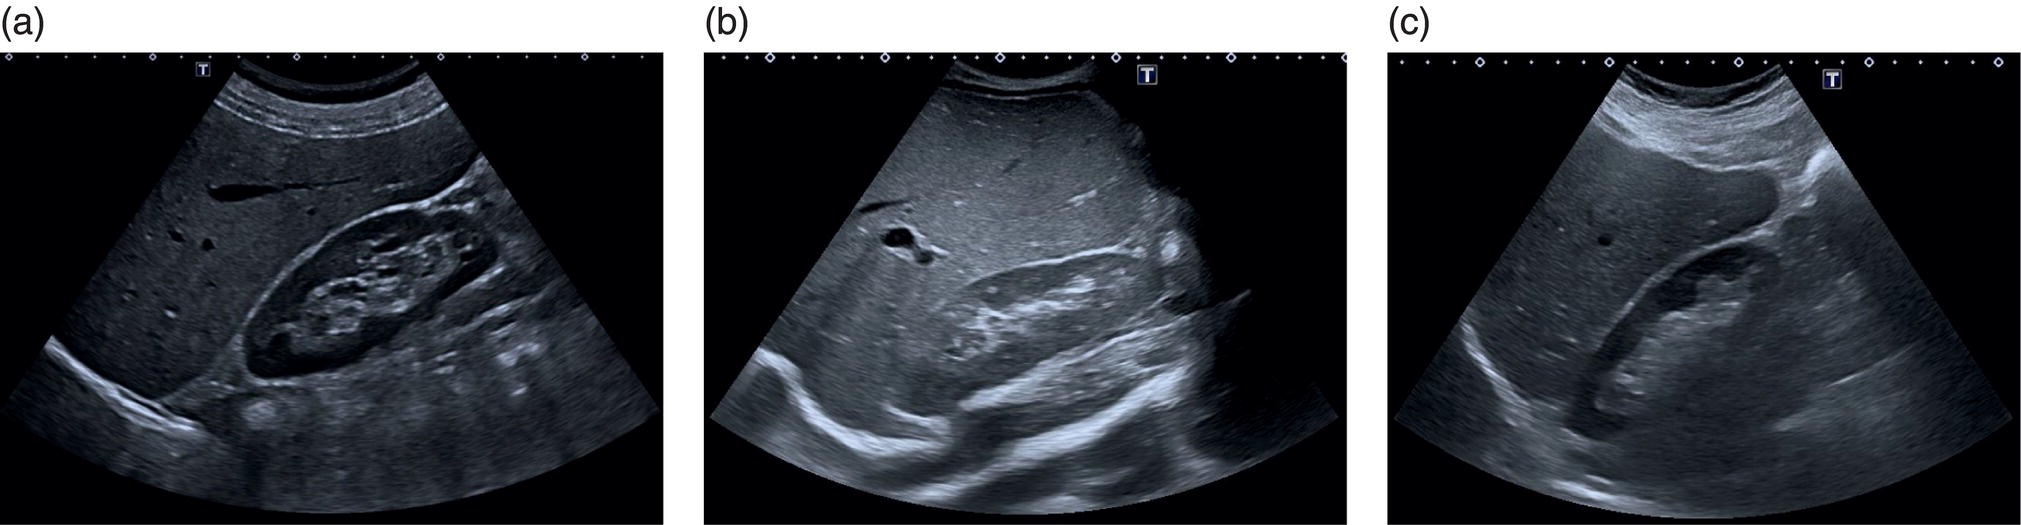

A máj mérete nehezen megítélhető és sokszor szubjektív módon történik. A vizsgáló orvos általában azt figyeli, hogy a máj alsó pólusa meghaladja-e a jobb vese alsó pólusának szintjét, illetve, hogy a máj széle lekerekített-e. Ha ezeket tapasztalja, felveti a májmegnagyobbodás lehetőségét (2. kép).

A máj határai (kontúrja) sima, az alsó széle "hegyes". Amennyiben ettől eltér, az utalhat valamilyen betegségre. (2. kép) Az előző bekezdésben említettük a májmegnagyobbodást, ilyen esetben a máj alsó széle lekerekítetté válik, ugyanakkor pl. májcirrózis (májzsugor) esetében a felszín szabálytalan lesz. Olyan esetekben mikor a májban valamilyen körülírt elváltozás van, pl. tumor, vagy ciszta és ez a szerv határaihoz közel helyezkedik el, akkor ez szintén előemelheti illetve deformálhatja máj kontúrját.

Máj mérete

- (a) Normális méretű és szerkezetű máj melynek alsó széle alig haladja meg a jobb vese alsó szélét. Az echogenitása is nagyon hasonló a veséhez.

- (b) Itt megnagyobbodott májat láthatunk melynek széle túl enyhén ér a vesén illetve nagy mértékben lekerekített és echogenitása fokozott a jobb veséhez képest. Az ok zsírosodás.

- (c) A szokotthoz képest kisebb széle lekerekített szerkezete minimálisan durvább és felszíne egyenetlen. Ennek az oka cirrhosis.